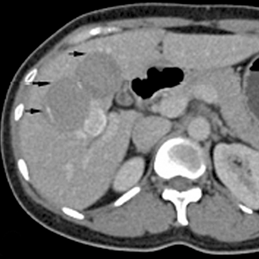

2. Tình huống thứ nhất là siêu âm có tổn thương nhưng không điển hình là ung thư gan nguyên phát (Hepatocellular carcinoma_HCC) cũng không điển hình là hình ảnh sán lá gan dạng abces đa ổ, hay tổn thương mới của sán lá gan lớn mà BS siêu âm vẫn còn can nhắc, trong khi đó kết quả xét nghiệm ELISA sán lá gan (+) và chỉ số bạch cầu ái toan tăng à nên bác sĩ sẽ quyết định là theo hướng điều trị sán lá gan lớn để cứu bệnh nhân hơn là điều trị theo hướng ung thư HCC vì bản thân HCC làm sao điều trị. Chúng tôi nghĩ đây là quyết định đúng của bác sĩ;

3. Tình huống thứ hai là siêu âm thấy tổn thương HCC nhưng kết quả xét nghiệm chỉ điểm khối u cho ung thư gan, loại alpha foetoprotein αFP (-), ELISA sán lá gan (+), biểu hiện lâm sàng nghĩ đến sán lá gan, như vậy đứng giữa hai tình huống đó, chúng tôi phải quyết định điều trị theo hướng sán lá gan là lựa chọn ưu tiên hơn là ung thư gan;